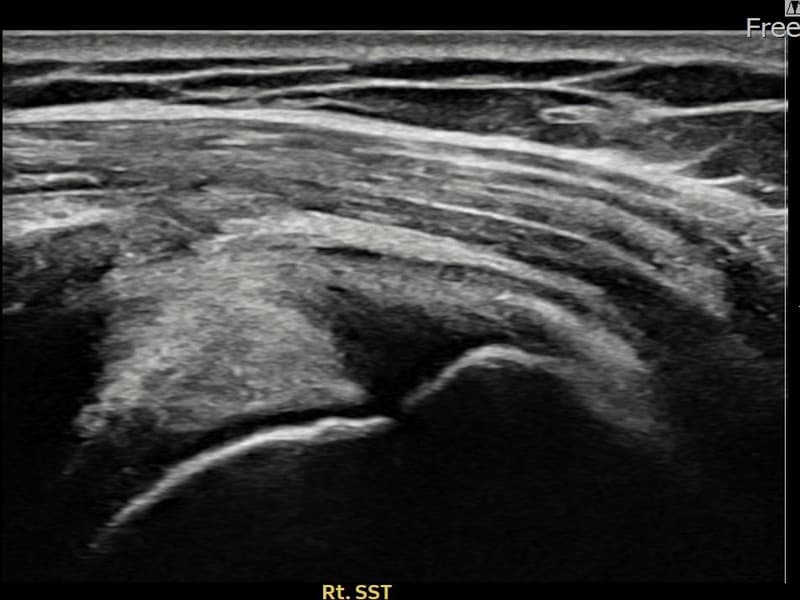

术前

术前超声确认右侧 冈上肌腱 滑囊面侧部分撕裂,右侧冈上肌腱回声不连续伴肌腱缺损(8mm × 4mm (肌腱厚度约35%缺损))。术后超声显示撕裂部位充满再生组织,肌腱连续性恢复,回声模式正常化。